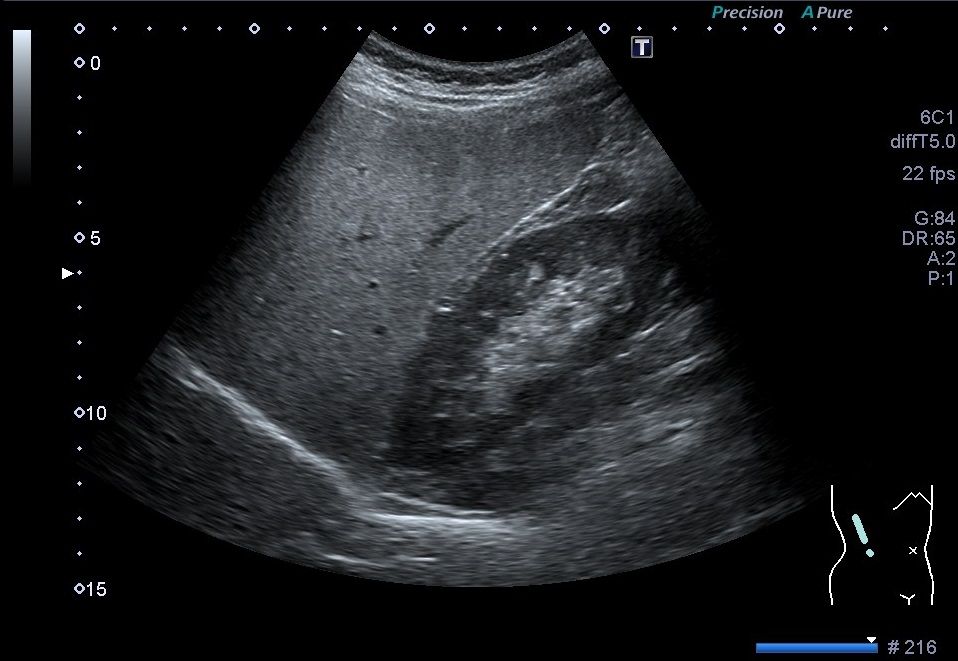

肝臓:肝実質のエコーレベルの上昇が認められる。(高輝度肝:bright liver)肝腎コントラストの上昇、深部でのエコー輝度の減衰、肝内血管の不明瞭化も認められる。

胆嚢周囲、門脈周囲にも限局性の低脂肪化域が認められる。

倦怠感の持続で来院し、腹部超音波検査を施行した患者である。アルコールの飲酒はなし。血液検査では肝酵素はASTが83U/l、ALTが157U/lとALT優位の上昇が認められ、γ-GTPは79U/lと軽度上昇、ChEは493U/lと正常範囲だった。

肝炎ウイルスはHBs抗原、HCV抗体はともに陰性だった。

脂質系はT-Choが243mg/dL、LDL-Choが172mg/dL、TGが224mg/dLが高値だった。

単純CTでは肝実質CT値の低下を認められ、脂肪肝の所見と合致した。

したがって非アルコール性脂肪肝(NASH)と診断された。

エコー図①

エコー図②